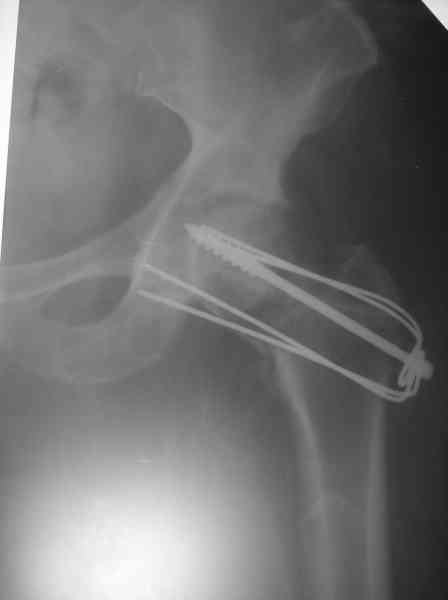

Где-то с 2001 г. начали оперировать шейки бедра, но теперь так же вынужден отказывать больным - сломался аппарат "Арман". Прооперировали пару больных по Вашему методу (Y-образными спицами). Но потом стали делать примерно так: 2-3 Y-образных спицы нанизывали на мощный винт и дополнительно перегибали ещё в одной плоскости. Затраты и оперативная агрессия примерно та же. Получается довольно жестко. Я Александру Николаевичу отосылал где то 1 год назад патент на изобретение. Прооперированно в настоящий момент 5 больных, к сожалению в 1-ом случае пришлось удалить фиксаторы из-за психоза через неделю после синтеза. В 2-х случаях переломы сраслись конечность опороспособная, в одном случае перегиб винта (к сожалению пришлось испоьзовать вместо винта стержень от аппарата довольно тонкий). А вообще-то эта проблема на уровне городских, ЦРБ, как система лечения не решена, в основном конечно в организационном плане. Хотелось бы, чтоб руководители нашего здравоохранения задумались и конечно внесли бы остеосинтез шейки в стандарты лечения. Посылаю снимок через 3 месяца после синтеза.